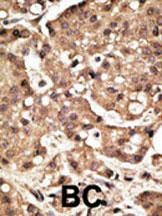

Formalin-fixed and paraffin-embedded human cancer tissue reacted with the primary antibody, which was peroxidase-conjugated to the secondary antibody, followed by AEC staining. This data demonstrates the use of this antibody for immunohistochemistry; clinical relevance has not been evaluated. BC = breast carcinoma; HC = hepatocarcinoma. |